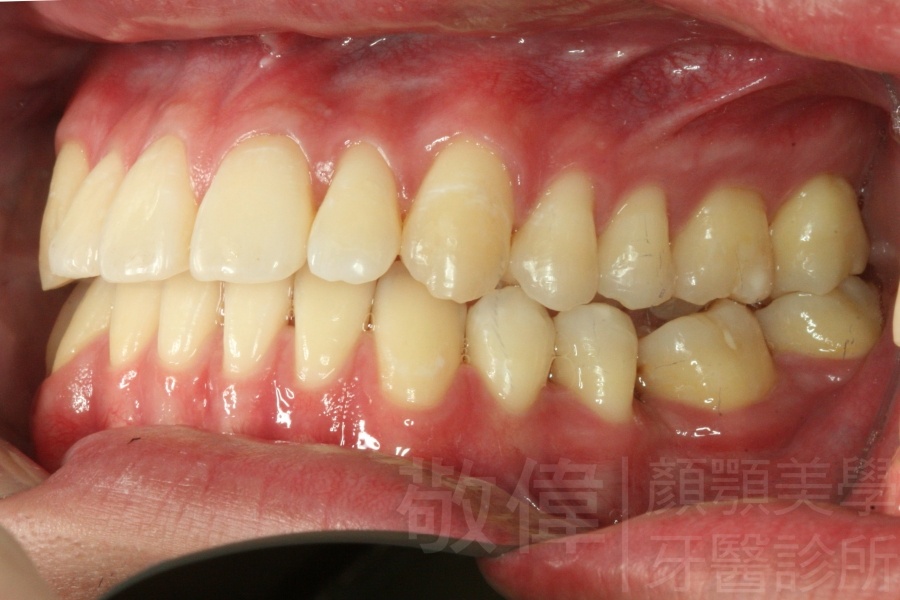

齒顏矯正/變臉矯正-月亮妹 變身 陽光正妹

變臉矯正,原來戽斗妹跟大歪臉變成自信正妹

經由本院3D數影X光影像儀分析、與3D齒顎顏矯正技術,再配合口腔顎面正顎專科醫師施以正顎手術治療,雙方共同合作,使患者臉部外觀有很好的改善,大歪變小歪,產生了天南地北的大改變,她的人生也整個變得不一樣。

因為矯正與正顎手術的配合,使「戽斗妹」變成了「陽光正妹」,完全的改變了她的人生,在面對各種場合、與人交際都散發出自信微笑。所以,奉勸家長,如果小朋友有臉顎畸型的問題,應該考慮配合做這種簡單、安全、有效的正顎手術。